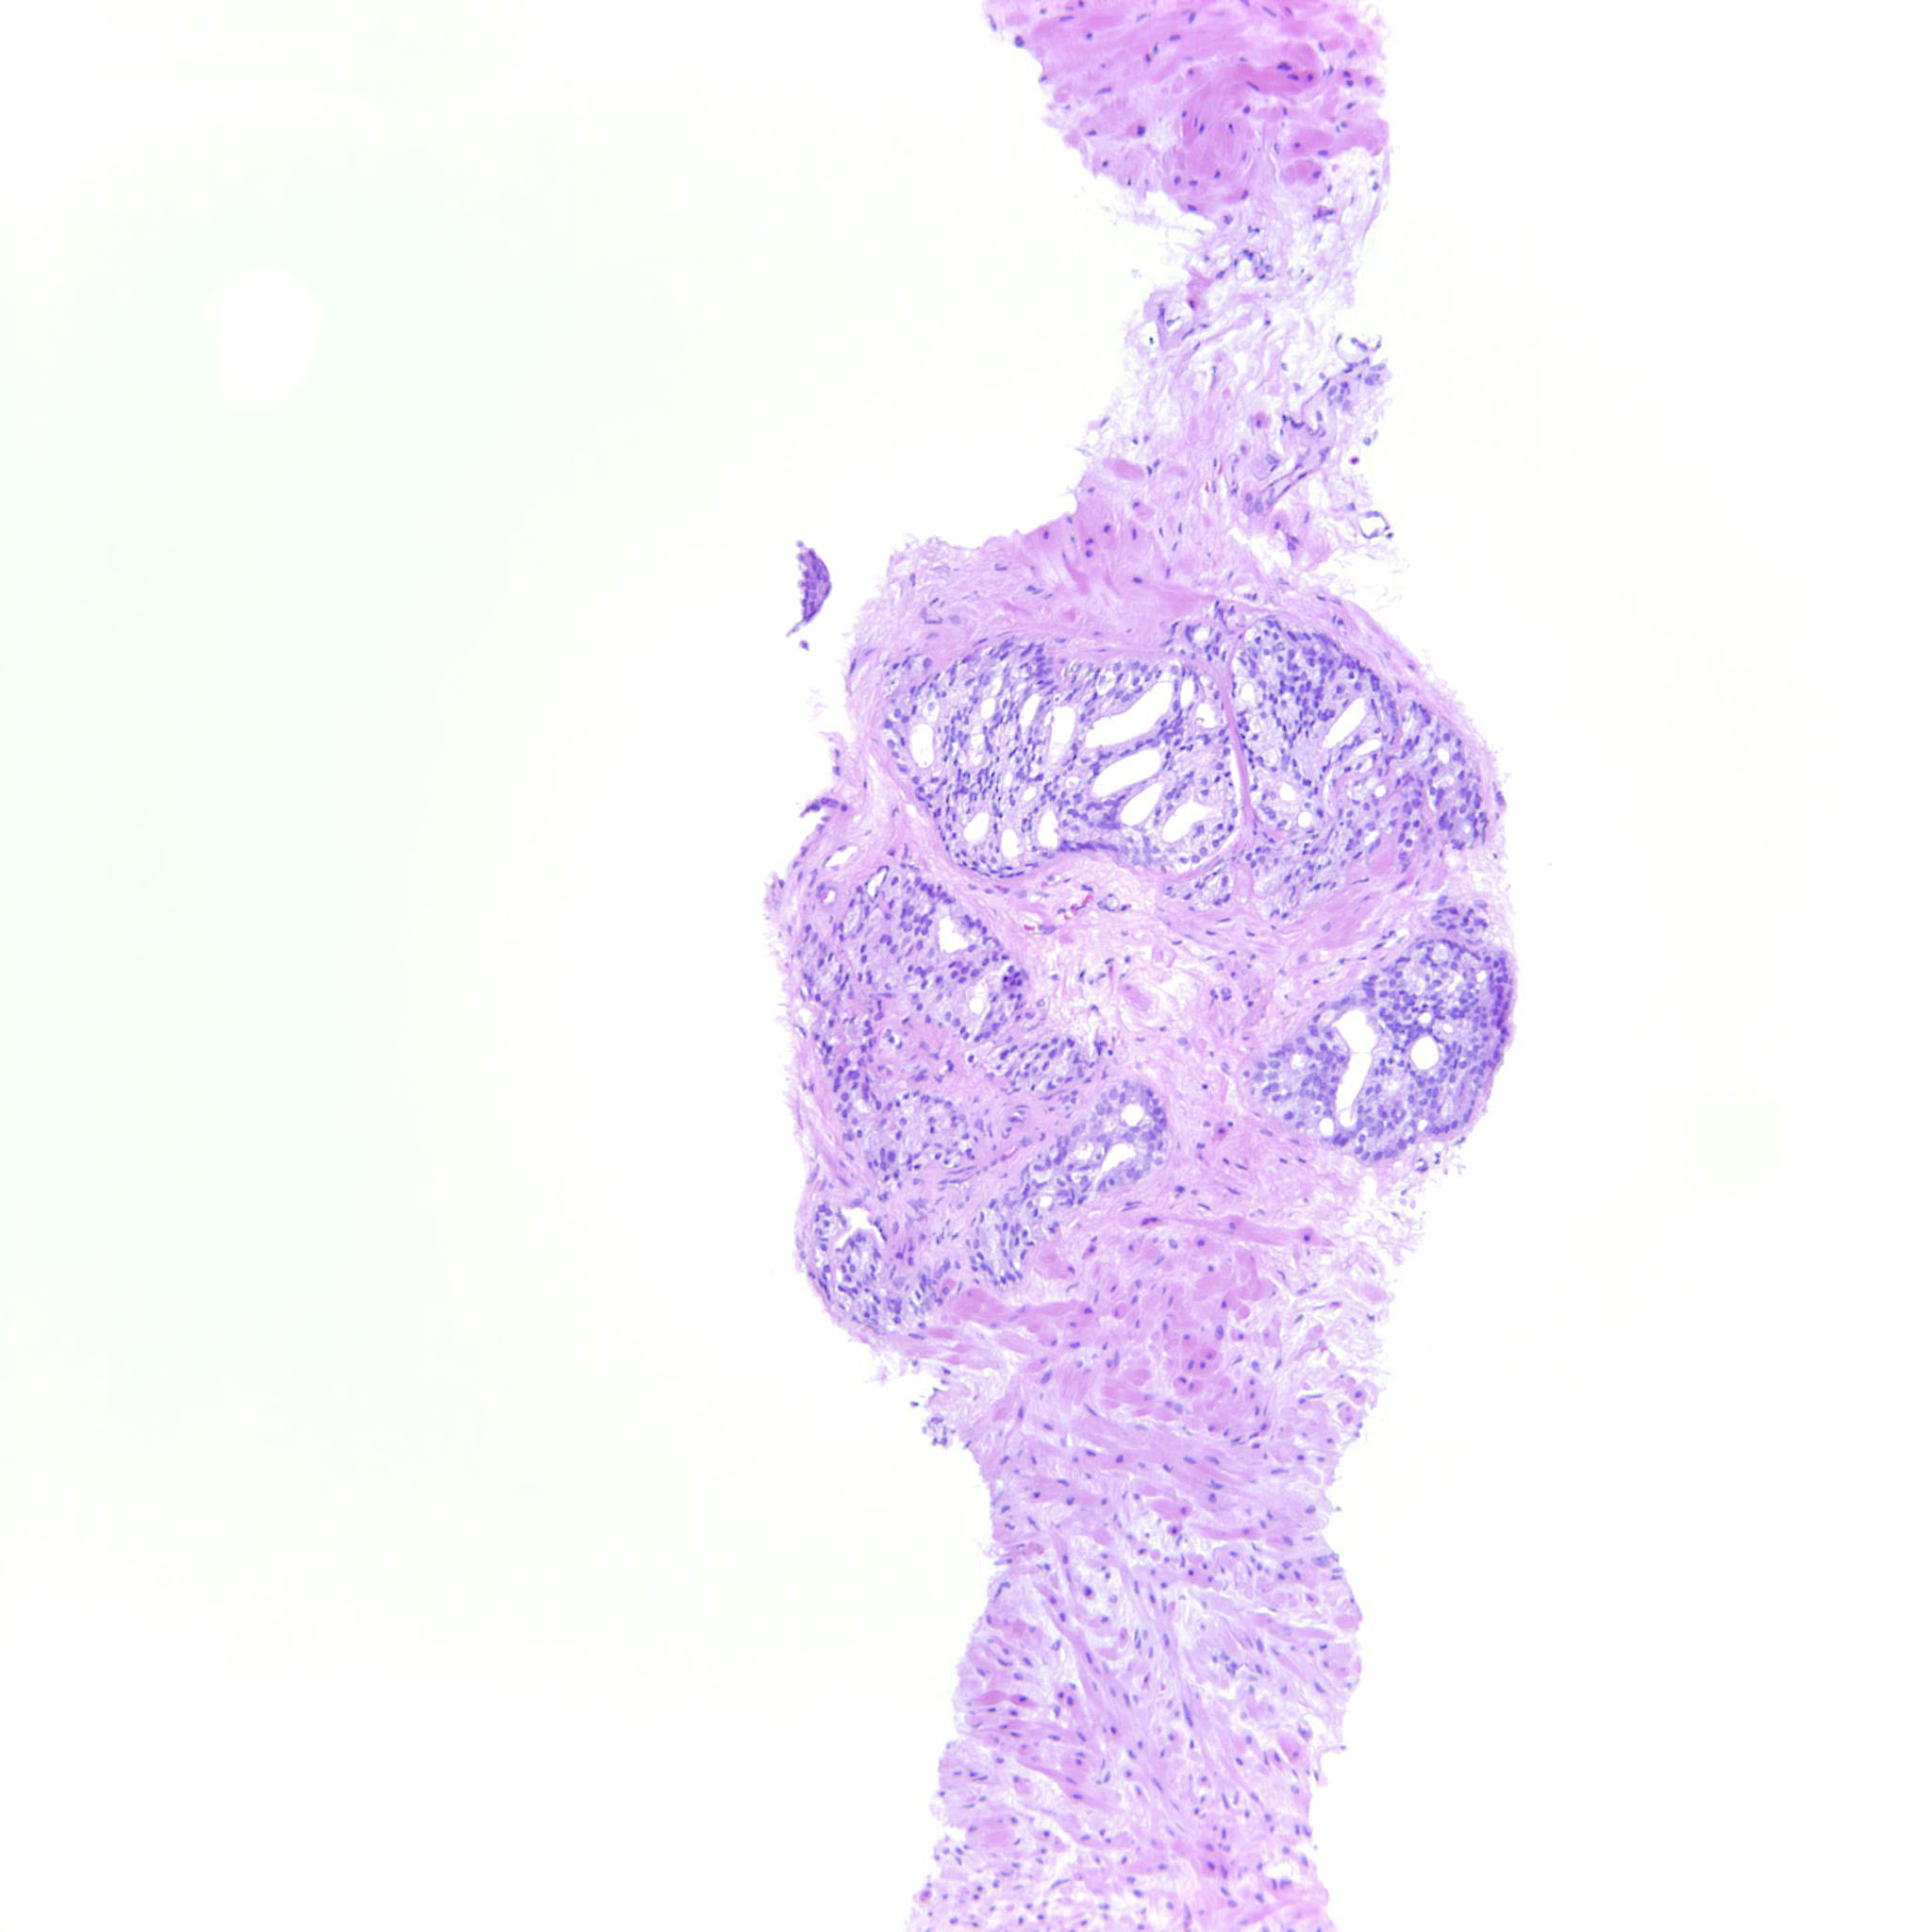

Prostate cancer grading

Case ID: 275